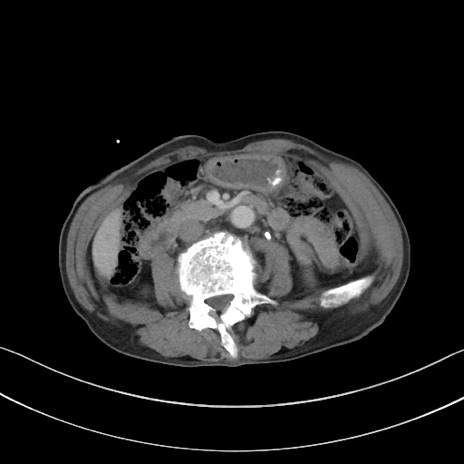

症例3(横断像)

【症例】 70歳代男性

【主訴】右鼠径部腫瘤、疼痛

【現病歴】本日朝より上記主訴あり、受診。

【既往歴】膀胱癌にて膀胱全摘、両側尿管皮膚瘻

【データ】WBC 5600、CRP 0.56